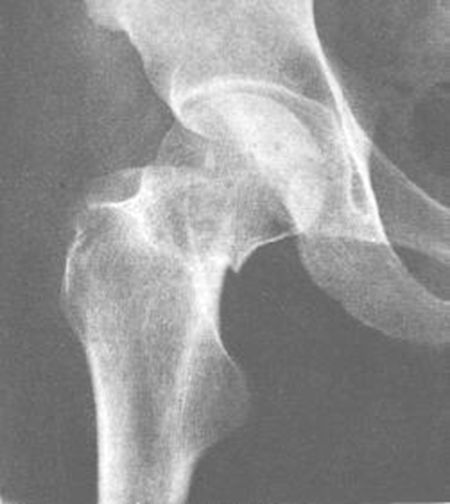

髋关节后脱位

髋关节前脱位

先天性髋脱位

常见髋关节测定线